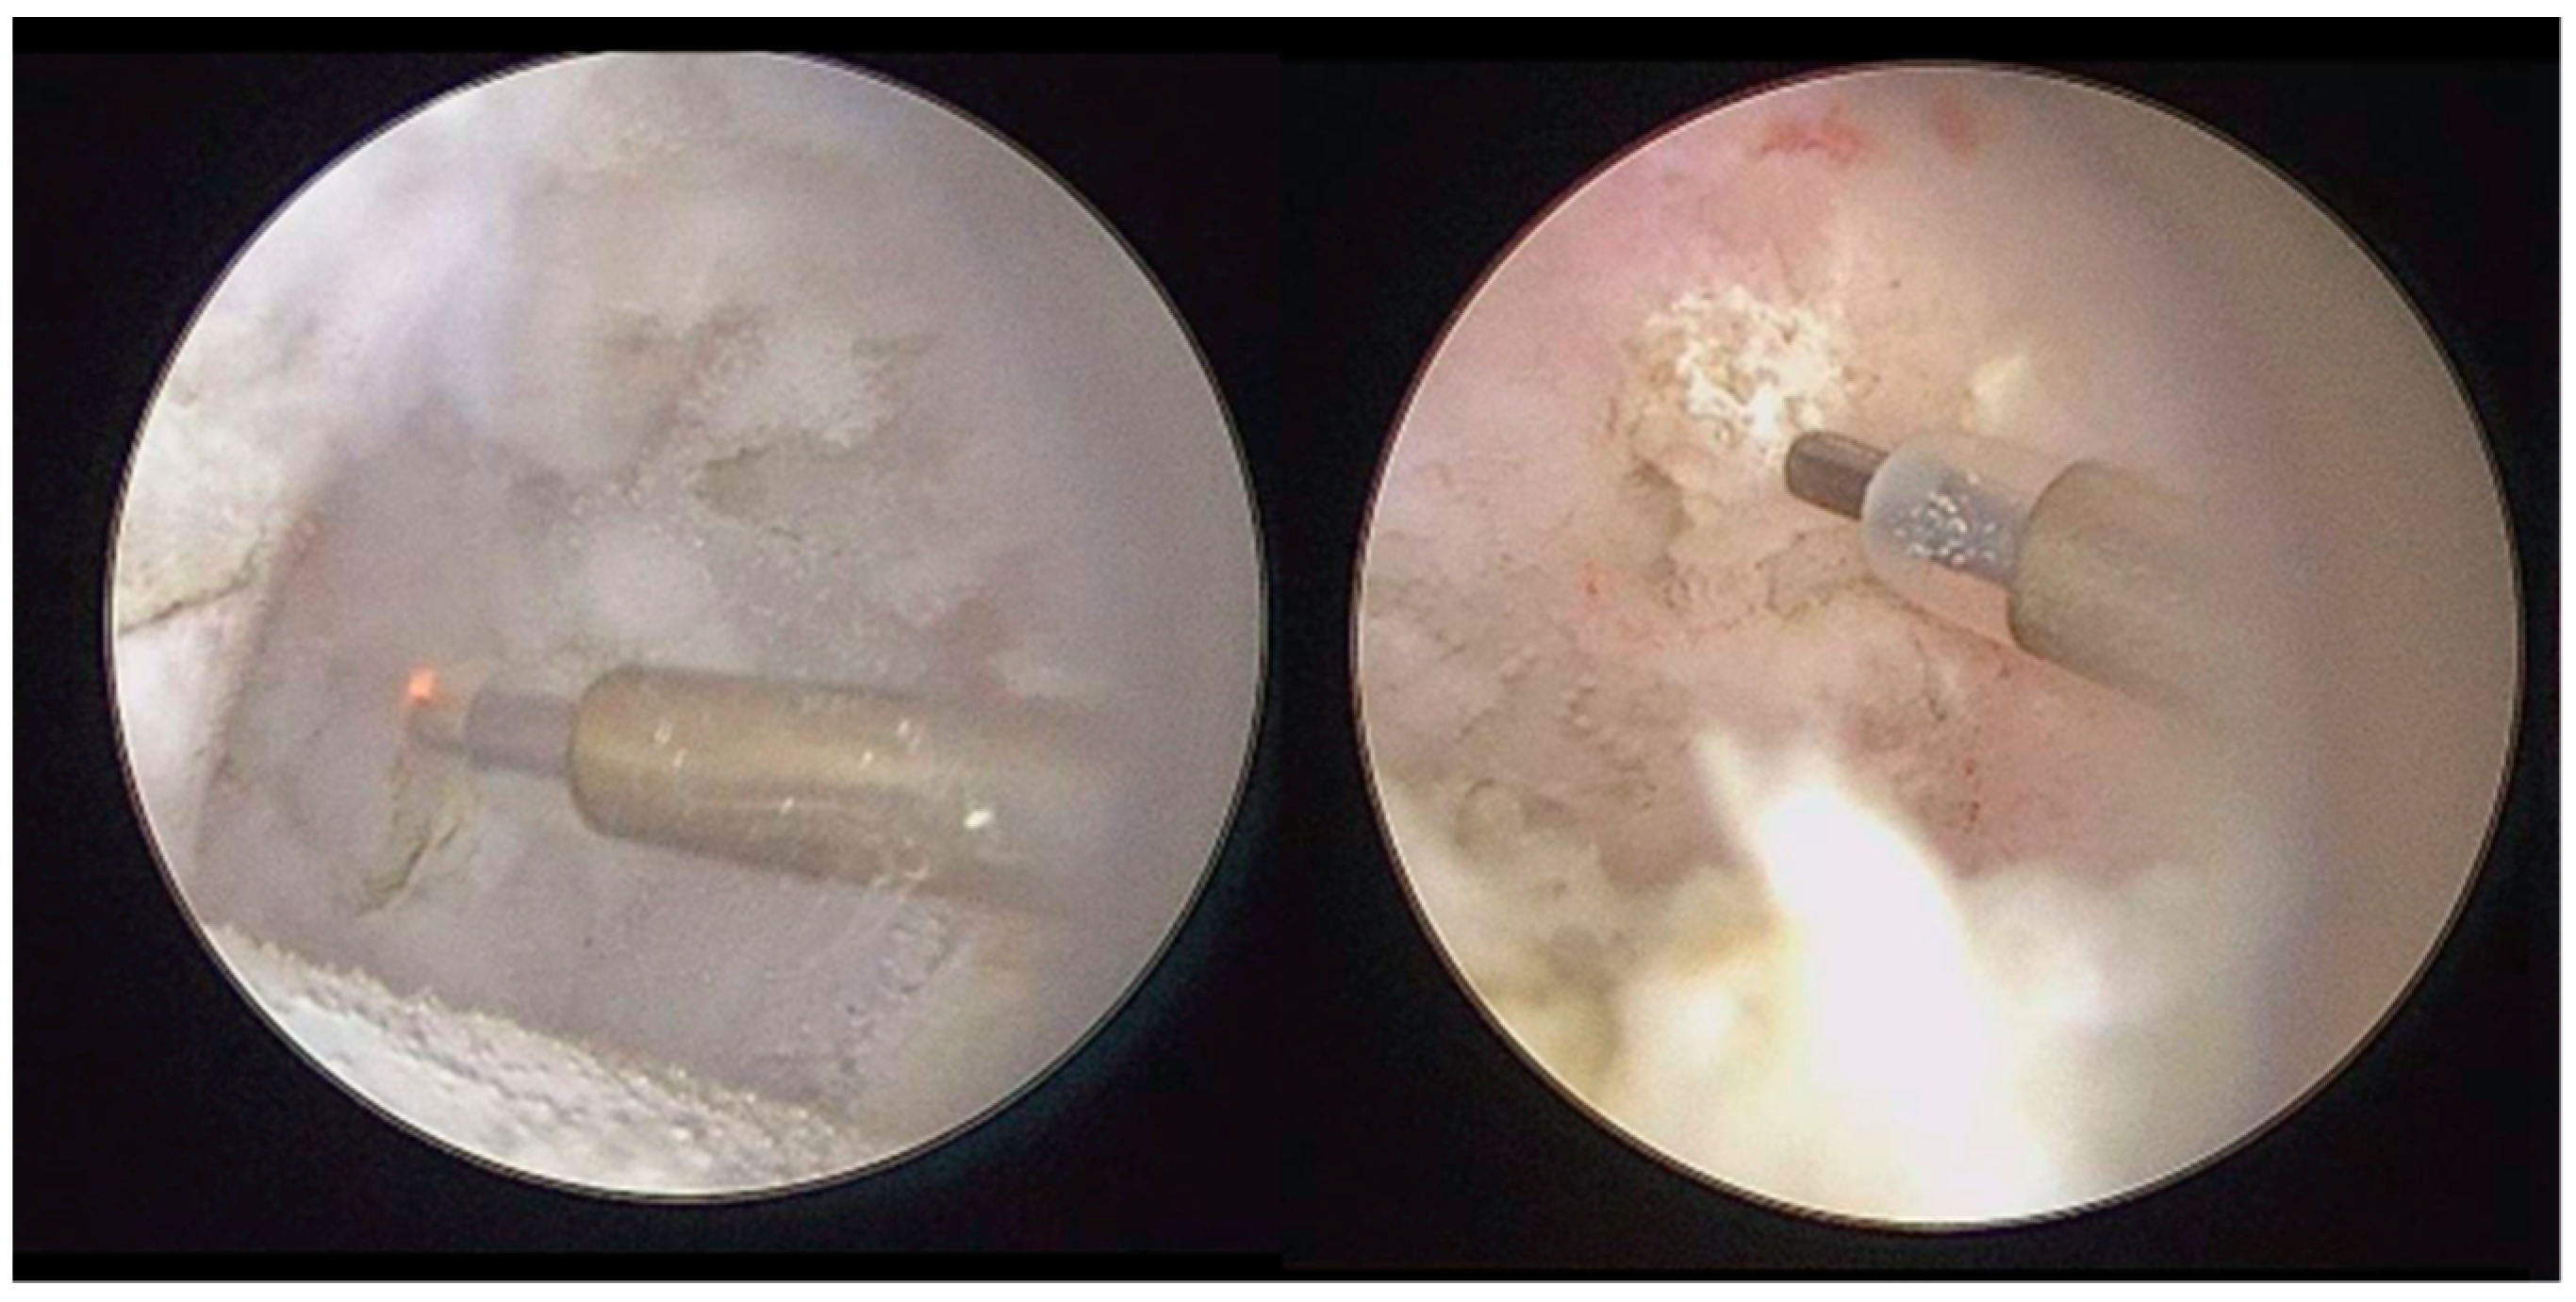

Figure 6.

Coblation of metaplasic nodules and division of large LBs to ease their washout.

Figure 7.

Coblation treatment of the metaplasic synovia, performing the so-called selective synoviectomy.